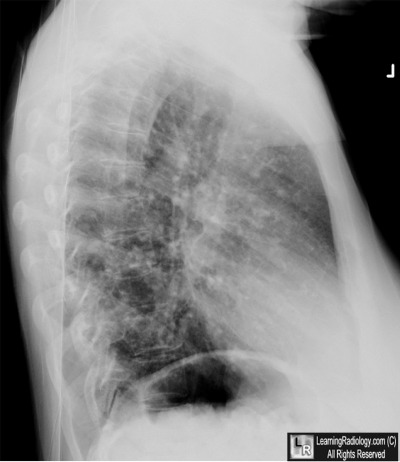

Additional Images - Lateral radiograph of chest

Lateral radiograph of chest